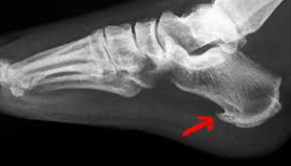

Patní ostruha a plantární fascitida

Ostruha patní kosti trápí lidi používající nesprávnou obuv, dále ty, kteří patu trvale přetěžují chybným stereotypem chůze nebo běhu. Ostruha patní kosti může být pozůstatek poranění paty a taktéž součástí skupiny revmatických chorob.

K nejčastějším příznakům ostruhy patní kosti patří bodavá bolestivost v patní krajině, která se objevuje při nášlapu a mnohdy i při pouhém doteku paty a je lokalizována vprostřed paty, může vystřelovat do plosky. Dále se může objevit zarudnutí paty, otok a později i různé nárůstky v oblasti úponu Achillovy šlachy - "Haglundova pata"